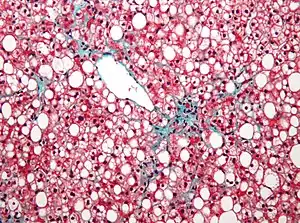

- Fatty liver disease (hepatic steatosis) is a reversible condition where large vacuoles of triglyceride fat accumulate in liver cells.[8] Non-alcoholic fatty liver disease is a spectrum of disease associated with obesity and metabolic syndrome.[9]